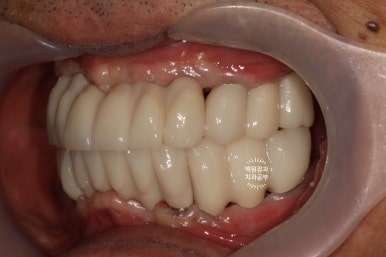

그리하여 완성된 최종보철물입니다!!

옛날부터 임플란트 틀니용으로 사용하시던 임플란트 3개는 임플란트 주위염이 조금 있어 약~간 쇠기둥 색깔이 보인다는 단점이 있긴 하지만, 다른 임플란트들은 꽤나 예쁘게 제작이 되었네요.

위 아래 교합면 사진을 보시면, 과연 이게 임플란트인가? 싶으실거에요. 치아에 지르코니아 크라운을 붙인 것과 큰 차이를 못느낄 정도로 정말 자기 치아같이 예쁘게 제작된 임플란트 크라운을 보실 수 있습니다!!